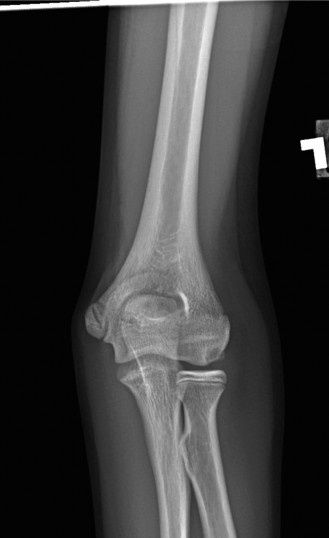

She has received multiple corticosteroid injections into her elbows over the past 3 years, but she no longer gets relief. Her images are shown (Figs. 2–99 to 2–102).

Figure 2–99

Figure 2–100

Figure 2–101

Figure 2–102

Approximately what percentage of patients with rheumatoid arthritis develop elbow involvement within 5 years?

The correct answer is (E). Between 20% and 50% of patients with rheumatoid arthritis will develop elbow arthritis. Isolated presentation of the elbow is rare and only occurs about 5% of the time. Care should be given to provide the best treatment for the entire upper extremity when evaluating and treating a patient with rheumatoid arthritis.

Which of the following is the procedure of choice when treating an advanced, debilitating rheumatoid elbow?

The correct answer is (E). Semi-constrained total elbow is the definitive procedure of choice when treating an elbow with extensive articular damage and subluxation or ankylosis of the joint (see Fig. 2–103). Rheumatoid patients place a lower demand on the prosthesis than patients with primary osteoarthritis (OA), and thus have a lower incidence of mechanical loosening. Due to the ligamentous laxity, prosthetic instability is the complication that most commonly inhibits success.